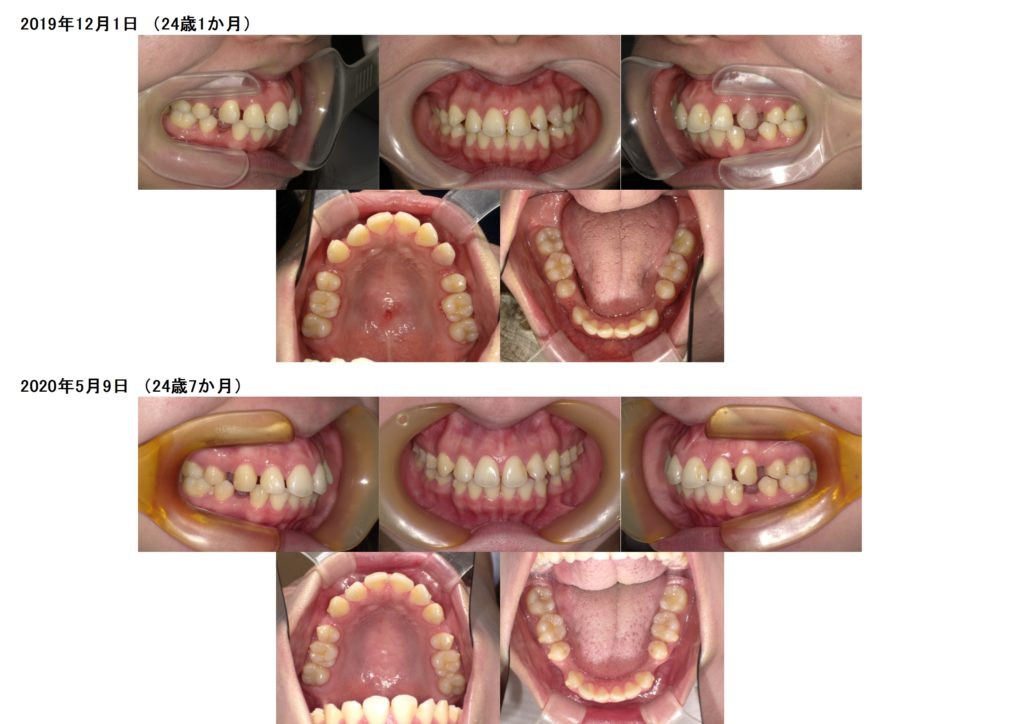

お口元が気になると来院された患者様です。

歯並び、噛み合わせは大きなズレはありませんが、上下の突出が気になる所です☺

↑上下の歯を抜きました。

奥歯の噛み合わせを治しつつ、少しずつですが歯が移動しているのが分かると思います。

上下の土台の変化もわかりますね☆